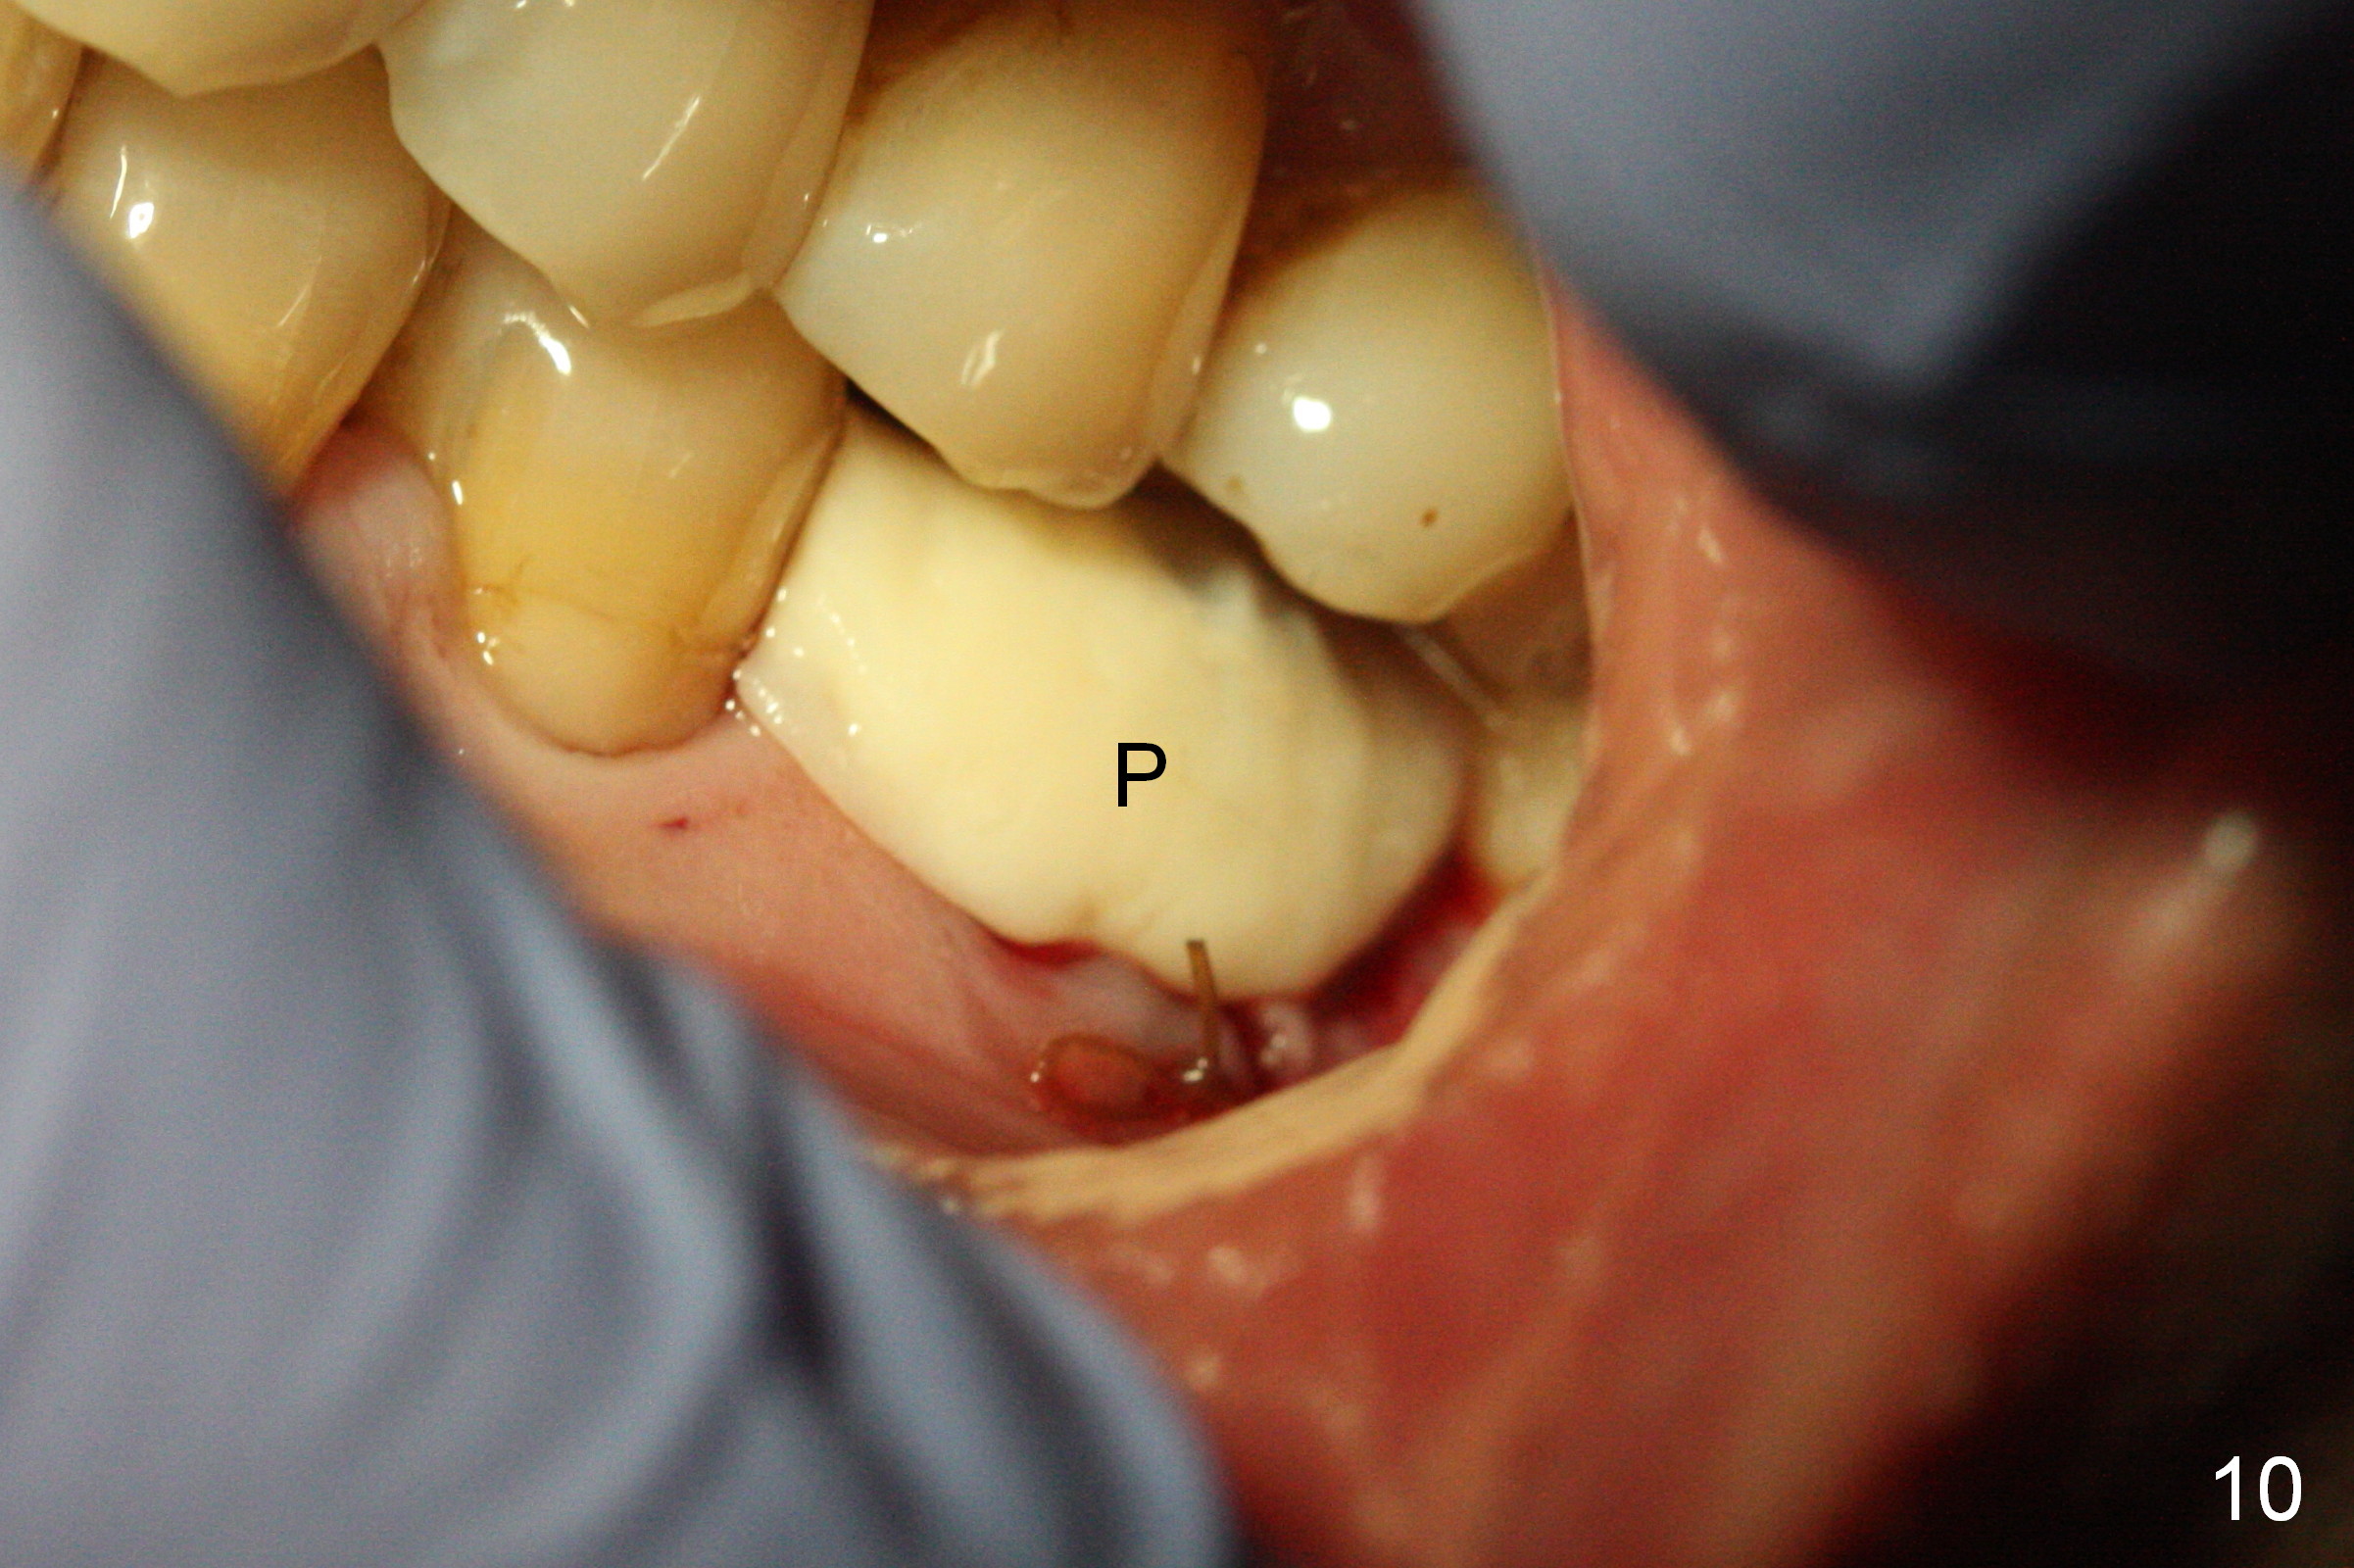

The asymptomatic tooth (#19) has a midbuccal fistula (Fig.1 <). The mesiobuccal pocket is 10 mm with purulent discharge from the sulcus (Fig.2,3). The mesiobuccal wall defect is confirmed when the tooth is extracted. Osteotomy is initiated lingually in the septum following septal crestoplasty (flattening) (Fig.4: using 1.6 mm drill for 9 mm). Since the lingual portion of the osteotomy is higher, it is difficult to use drill with stopper. For the narrow septum osteotomy, multiple drills are used sequentially (Fig.5 after 4.3 mm drill). A 4.5x11 mm dummy implant is placed (Fig.6) apparently too deep. When a 5x11 mm IBS implant is being placed, the depth is tightly controlled (Fig.7). The implant is apical to the lingual crest, whereas there is ~ 2 mm implant exposure buccally. That is, there is a large gap mesiobuccally (Fig.8), which is filled with .5-1.5 mm allograft (Fig.9 *). A 6.5x5.7(3) mm abutment (A) is placed and trimmed for an immediate provisional (Fig.10 P). The lacerated buccal gingiva is sutured as well as application of Perio Glue.